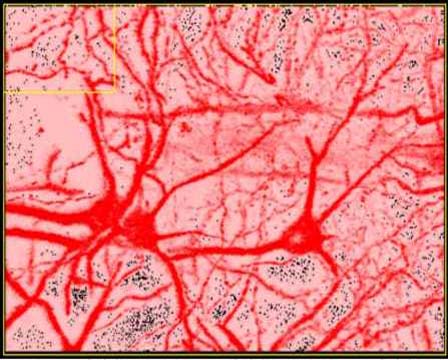

LCSM IMAGES

LCSM IMAGES[Laser Scanning Confocal Microscope System]